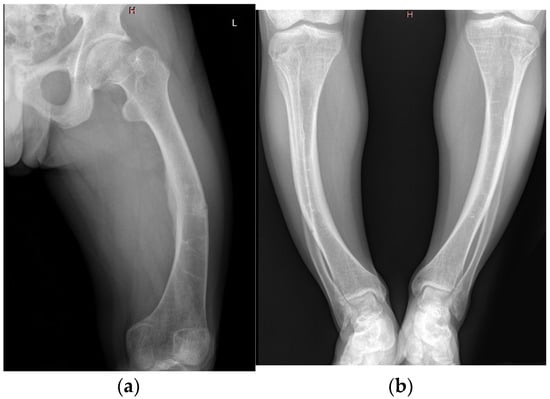

X-Linked Hypophosphatemia in a Family Cohort: Clinical Variability, Genetic Confirmation and Modern Therapeutic Perspectives

Background/Objectives: X-linked hypophosphatemia (XLH) is the most common form of inherited rickets, caused by pathogenic mutations in the PHEX gene (phosphate-regulating endopeptidase homolog, X-linked). These mutations increase fibroblast growth factor 23 (FGF23) activity, resulting in renal phosphate wasting and defective bone mineralization. The disorder manifests with variable skeletal, dental, and extraskeletal involvement. Conventional therapy with oral phosphate and active vitamin D offers limited benefit, whereas burosumab, an anti-FGF23 monoclonal antibody, has transformed disease management. Methods: The index case, a 43-year-old woman, remained undiagnosed until adulthood, leading to severe deformities, osteoarthritis, chronic pain, and complete edentulism. Her 55-year-old sister presented with a milder phenotype. The 20-year-old nephew, diagnosed in childhood and intermittently treated with phosphate and alfacalcidol, developed short stature, genu varum, and early degenerative joint disease. Following genetic confirmation, he began burosumab therapy, which normalized phosphate metabolism, reduced pain, and improved mobility. Results: XLH demonstrates marked intrafamilial phenotypic variability despite identical PHEX mutations. In this series, delayed recognition in adults led to irreversible skeletal deformities, osteoarthritis, and dental loss, whereas earlier diagnosis in the younger patient allowed timely intervention. Conventional therapy only partially mitigated complications, while burosumab achieved rapid biochemical correction and symptomatic improvement. This contrast highlights the importance of early genetic testing, family screening, and prompt initiation of targeted treatment. Conclusions: This family cluster underscores the critical need for early diagnosis, genetic confirmation, cascade screening, and lifelong multidisciplinary care. Burosumab represents a therapeutic paradigm shift in XLH, capable of altering disease trajectory when initiated early. Full article

Figure 1